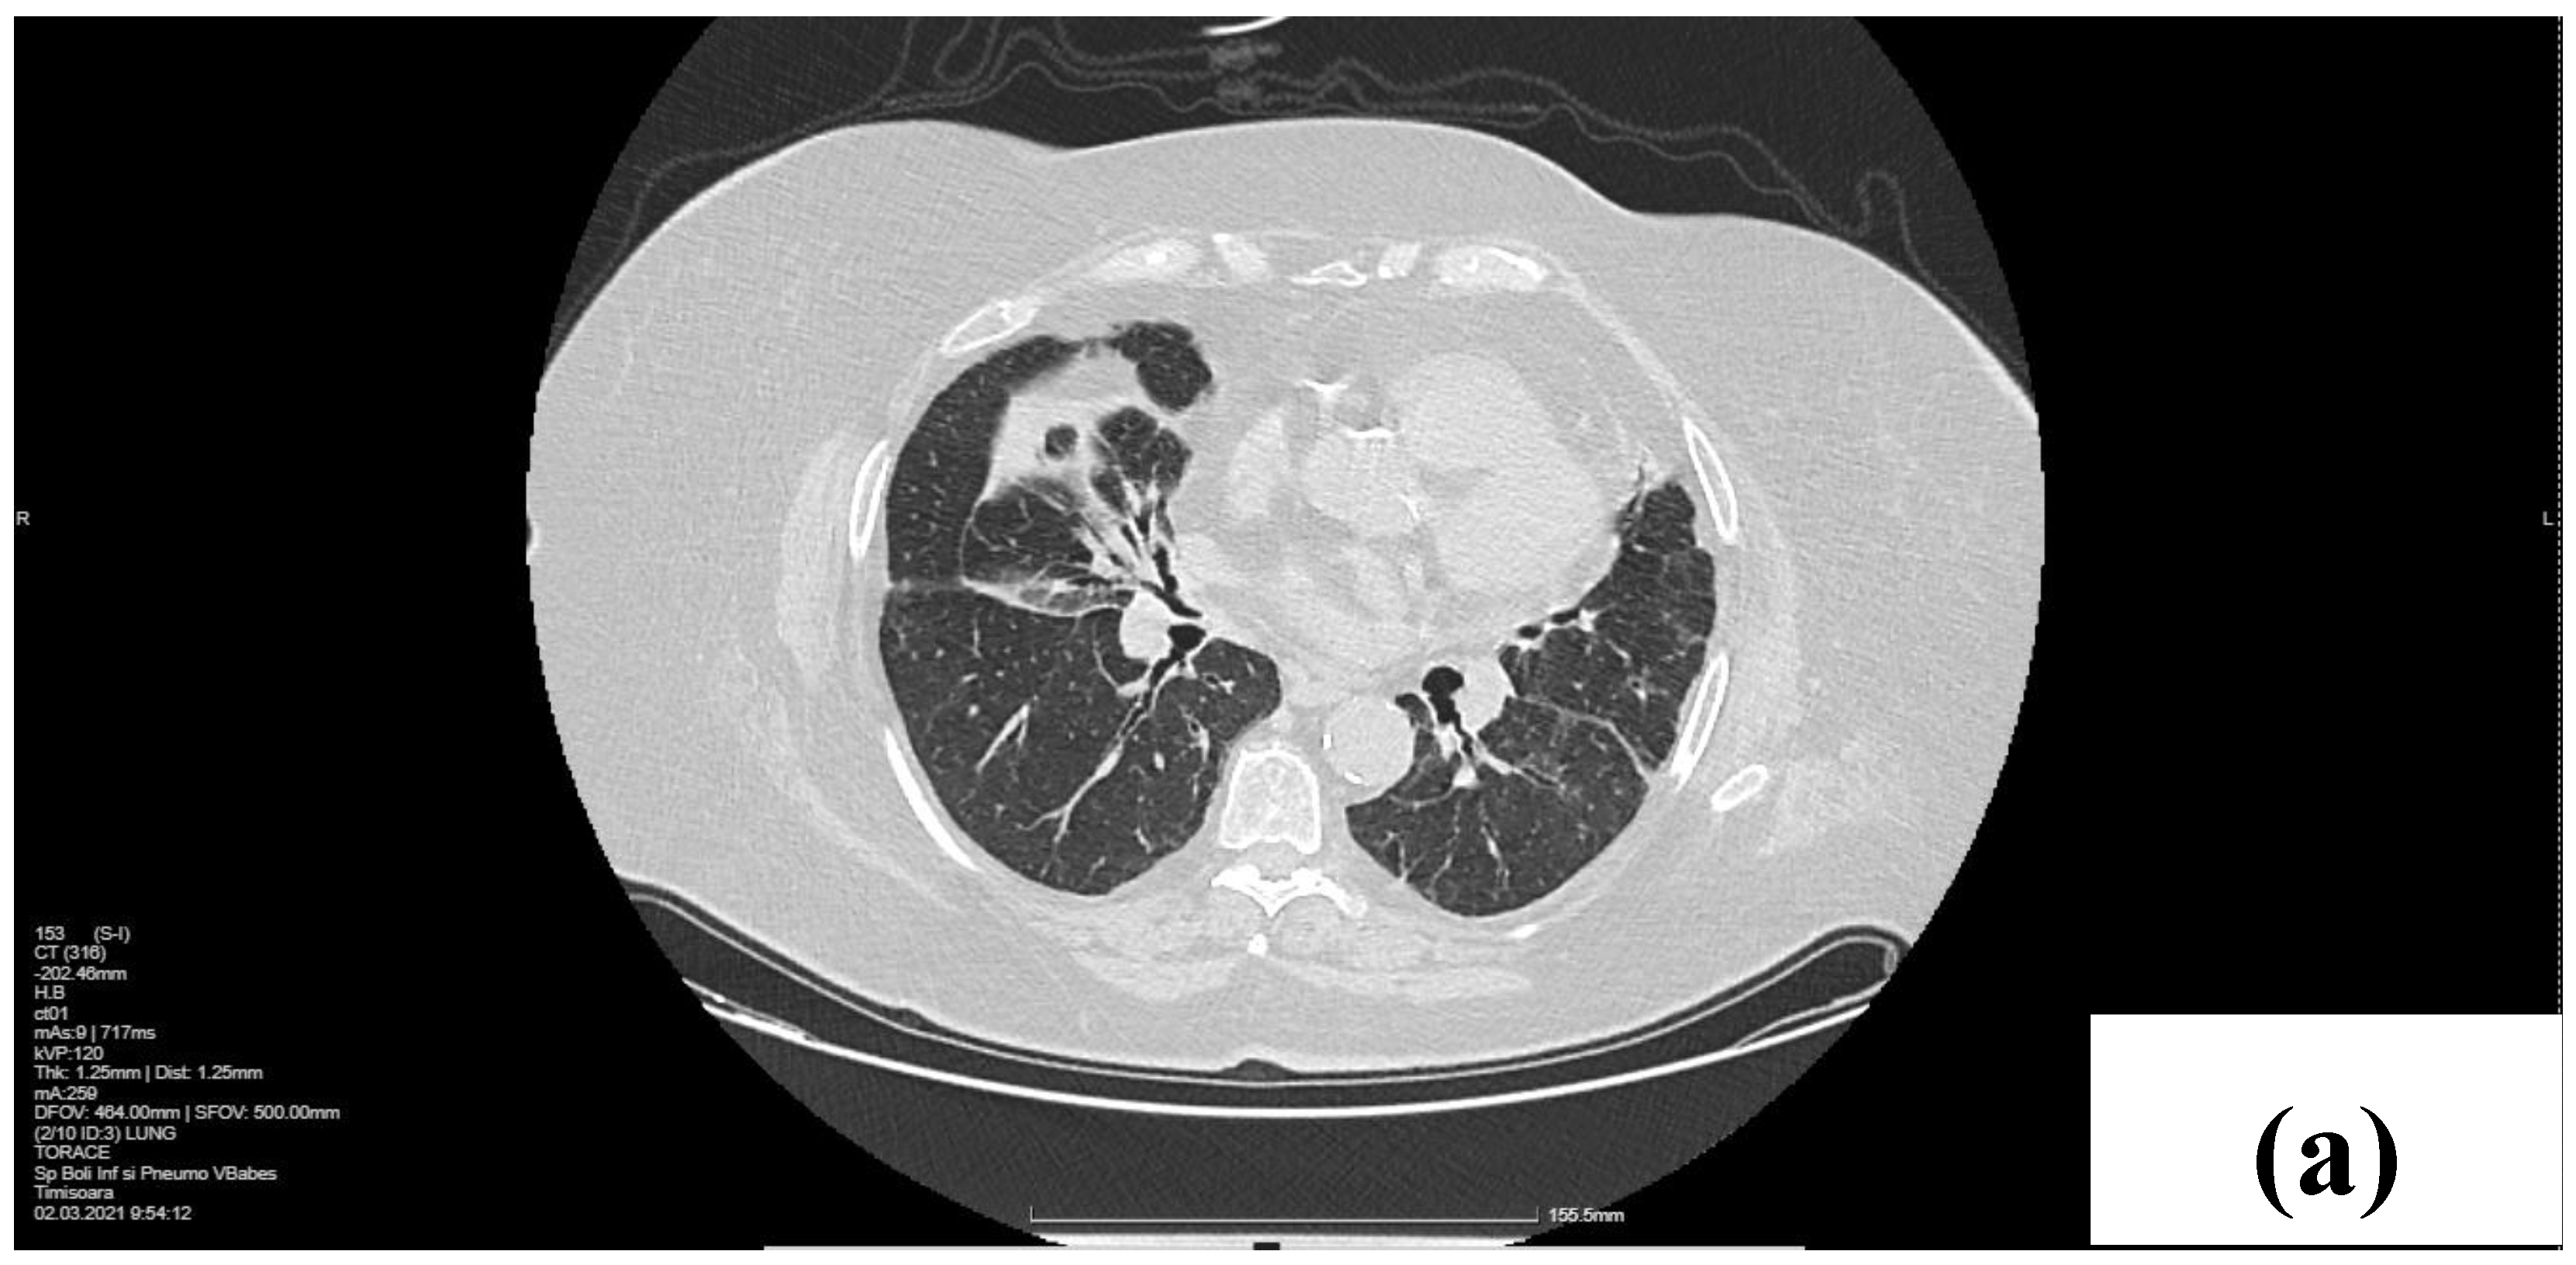

2.1. Laboratory, Radiological, and Histological Examinations